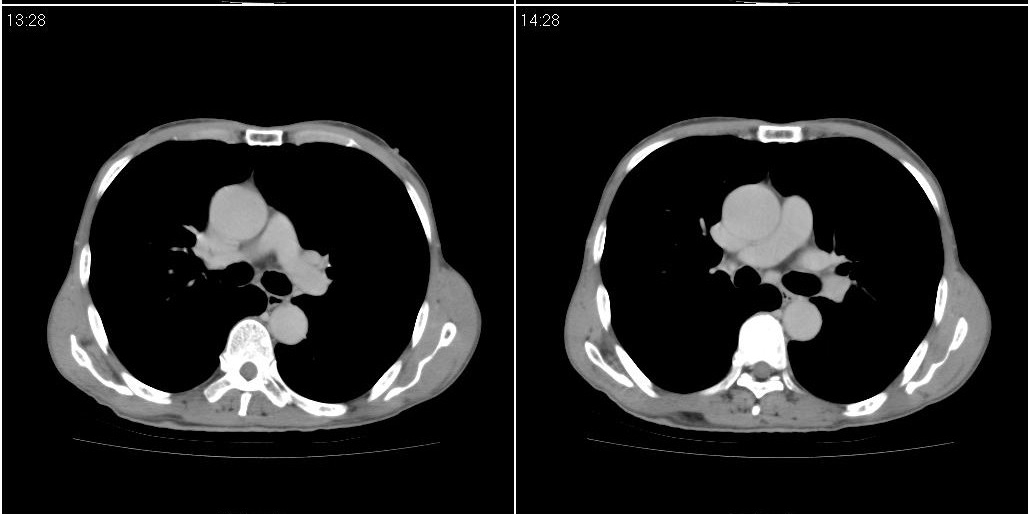

标题: CT25416:男性,70岁。胸片发现右下肺斑片状阴影

以下是ct检查的情况:

考虑右肺下叶炎症可能性大?未除占位,建议增强。右下肺肺不张

右下胸壁皮下气肿。